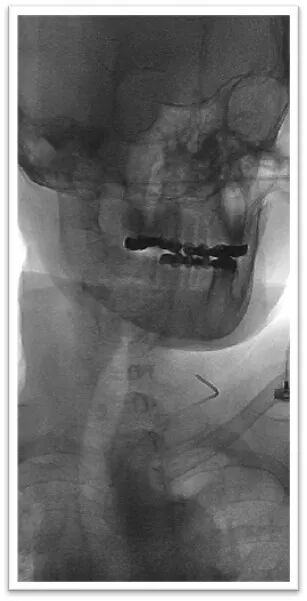

该患者胸主动脉迂曲,主动脉弓呈牛角弓,选择5F 125cm蒸汽塑形后在泥鳅导丝引导下同轴引导6F Neuron Max长鞘顺利置于左侧颈总动脉;